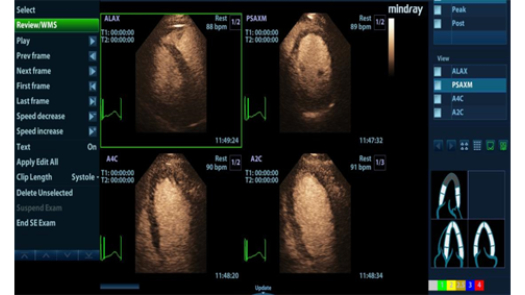

Stress Echo

- Поддержка нескольких протоколов нагрузки.

- Морфометрические показатели сердечной мышцы

- Поддержка визуализации при нагрузке благодаря контрастированию левого желудочка

- Стресс-эхоКГ: оценка перфузии и жизнеспособности миокарда